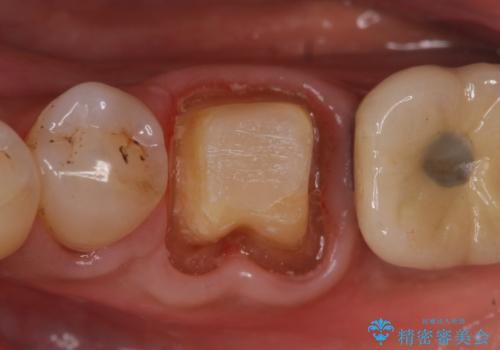

検査の結果、左下6番目の歯は神経が死んでおり根尖に病変が出来ていたため、根管治療を行いました。

その後症状の消失を確認後、オールセラミッククラウンによる補綴を行いました。

- オールセラミッククラウン…¥100,000、仮歯…¥10,000、ファイバーコア…¥20,000費用は治療当時の料金となります